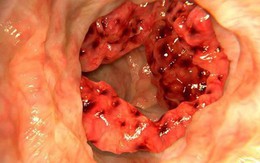

Ung thư đại tràng giai đoạn sớm rất ít triệu chứng, nhưng sau đó có thể xuất hiện 4 dấu hiệu

Ung thư đại tràng thường gặp ở người trên 50 tuổi, tuy nhiên những năm gần đây, tỷ lệ mắc tăng nhanh ở giới trẻ.

Ung thư đại trực tràng: Người và nghề nào sẽ có nguy cơ mắc bệnh cao?

Ung thư đại trực tràng đang có xu hướng gia tăng ở Việt Nam, đây là căn bệnh có sự liên quan trực tiếp tới vấn đề ăn uống kém khoa học.